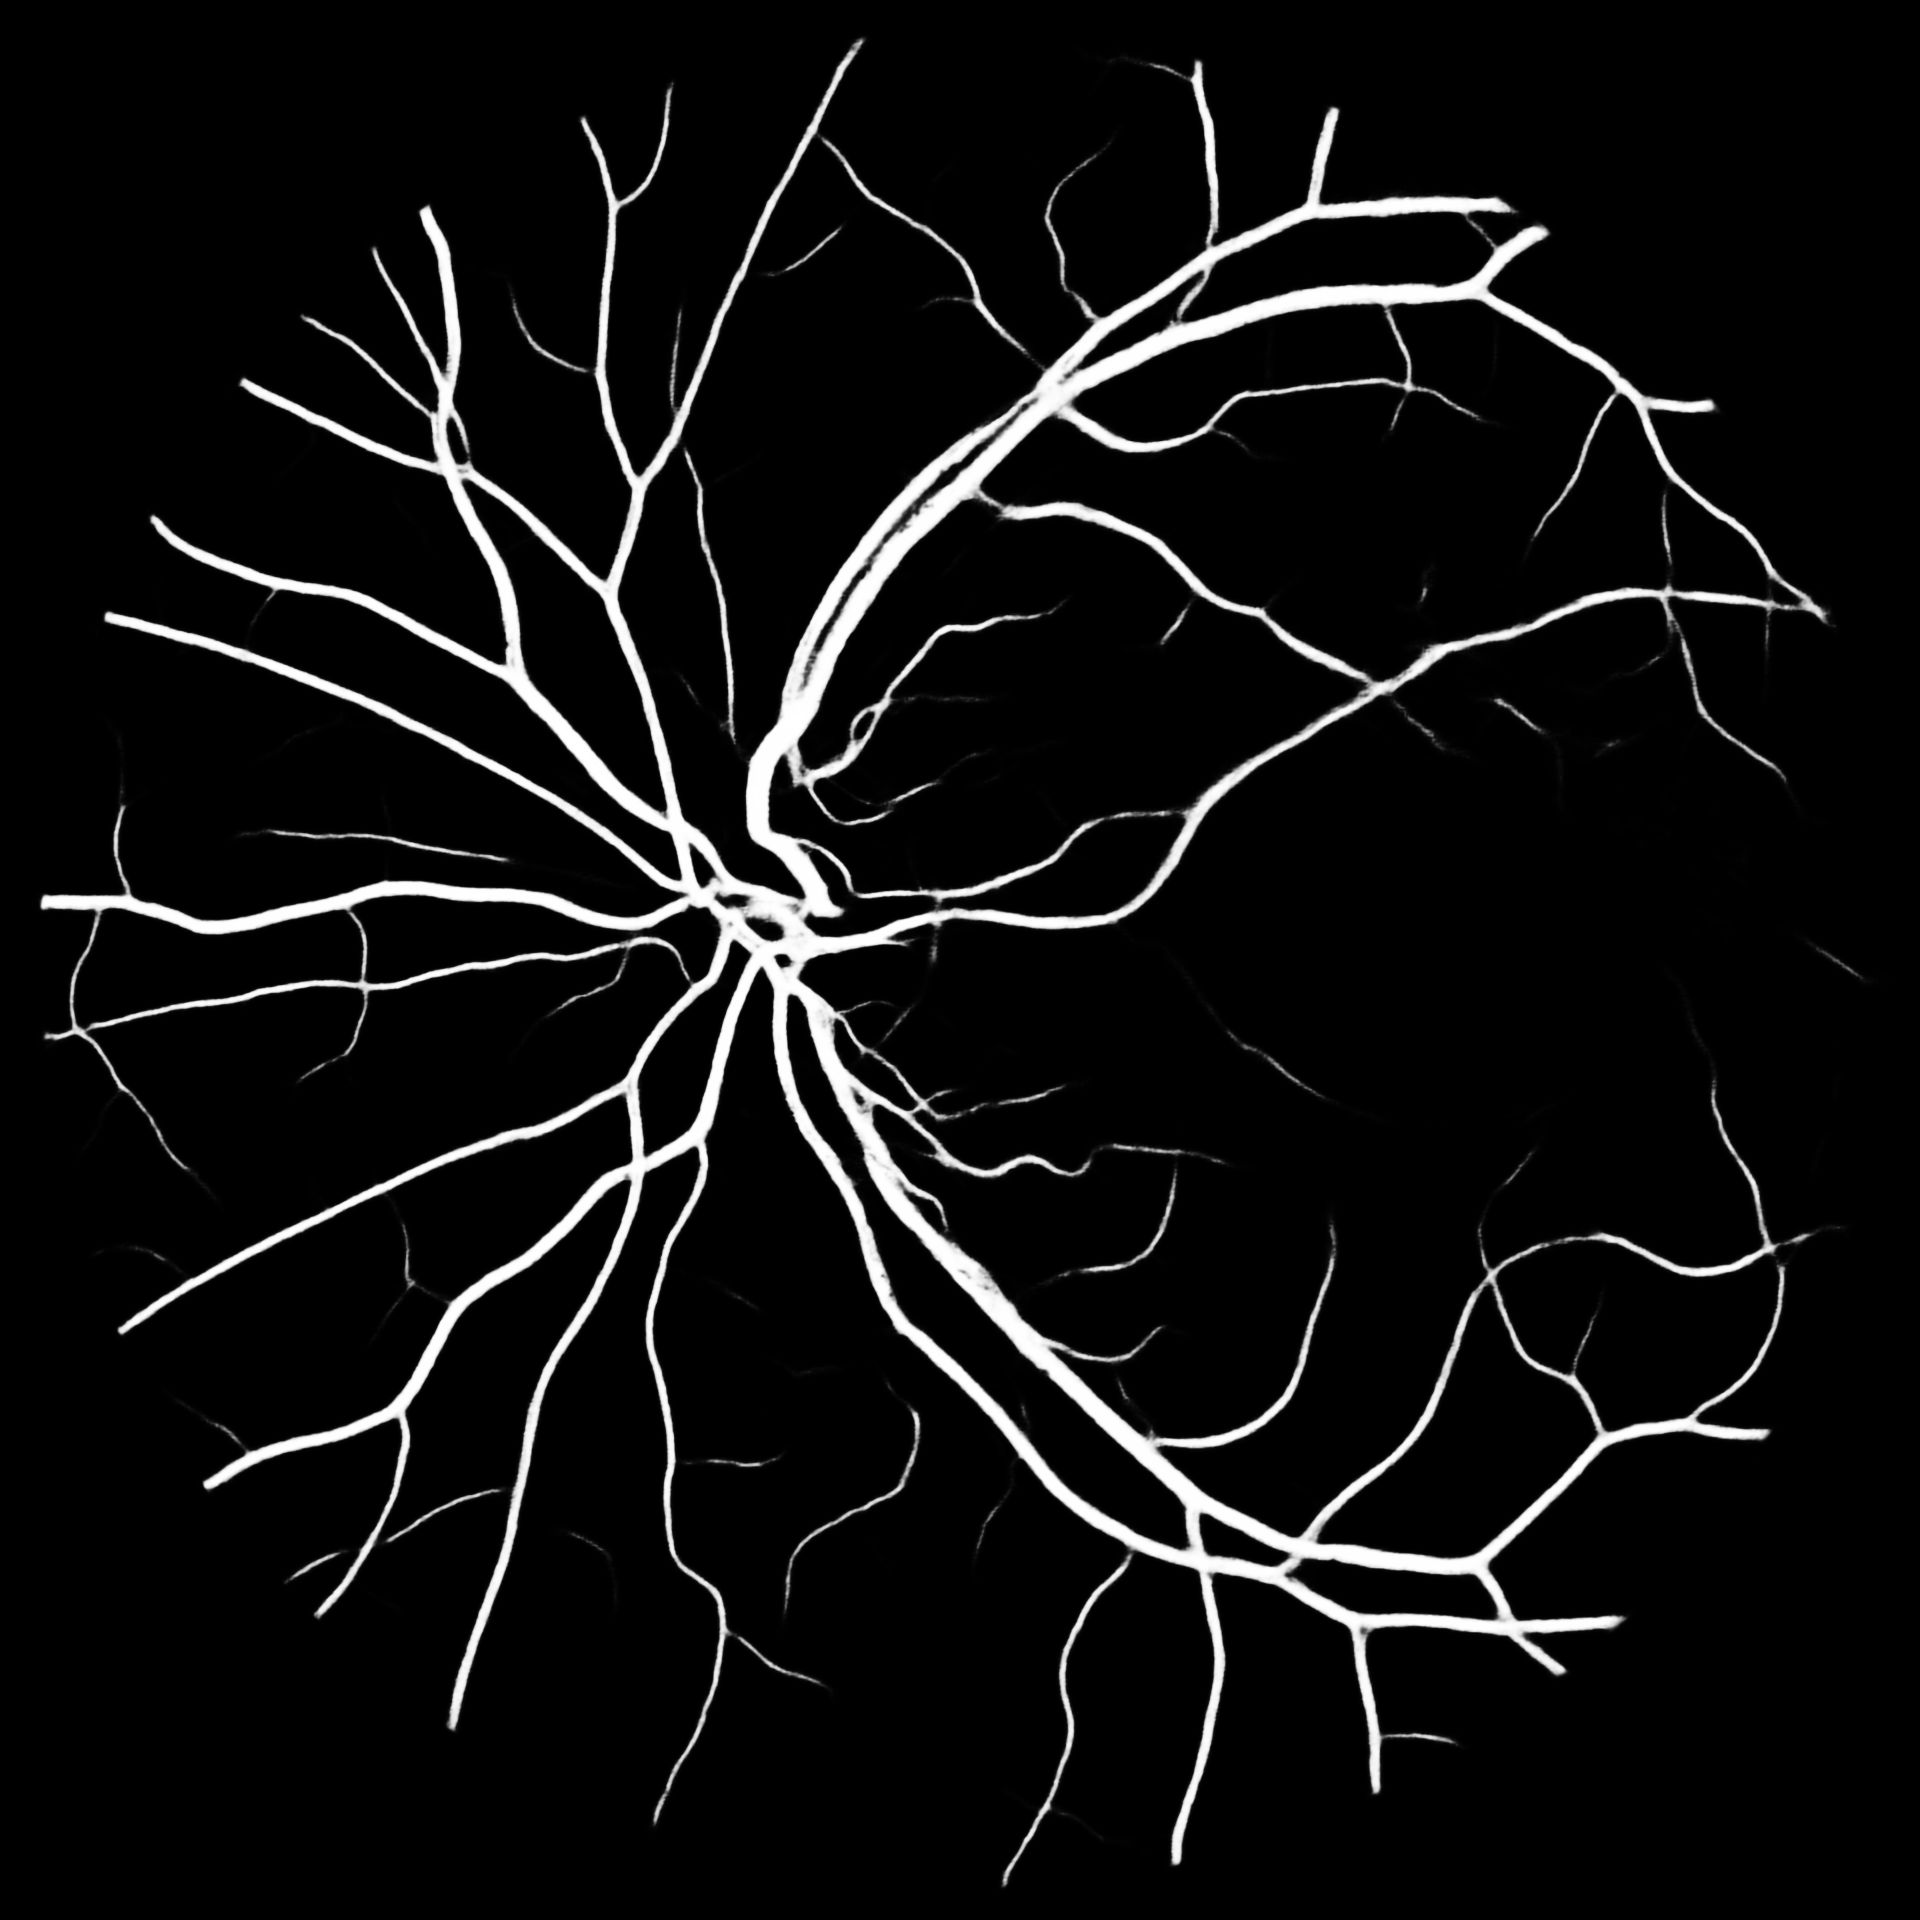

VI Evaluation

To put our results into perspective, Table V compares previous works to our methods. We report the -score for our results together with their standard deviation. Overall M2U-Net and DRIU trained on COVD are competitive, with the best performance on the high-resolution dataset HRF, where a new state-of-the-art F1-score could be reached. Additional metrics such as accuracy, sensitivity, precision and specificity are available in the documentation of our software package. Further, to the available public datasets, we trained M2U-Net on COVD for a private target dataset with a resolution of 1920x1920 for which no ground-truth data is available. The predicted vessel probability maps are displayed in Figure 5. While we can only make subjective statements, we find that the generated probability maps are of good quality, with the majority of main vessels being detected, even in presence of pathologies. An illustration of predicted vessel maps versus ground truths for M2U-Net on HRF is provided in Figure 4.

The authors would like to thank Dr. Christophe Chiquet from the University Hospital of Grenoble and Inserm, France, for providing the high-resolution retina fundus images in Fig. 5.

HRF

COVD

COVD– SSL